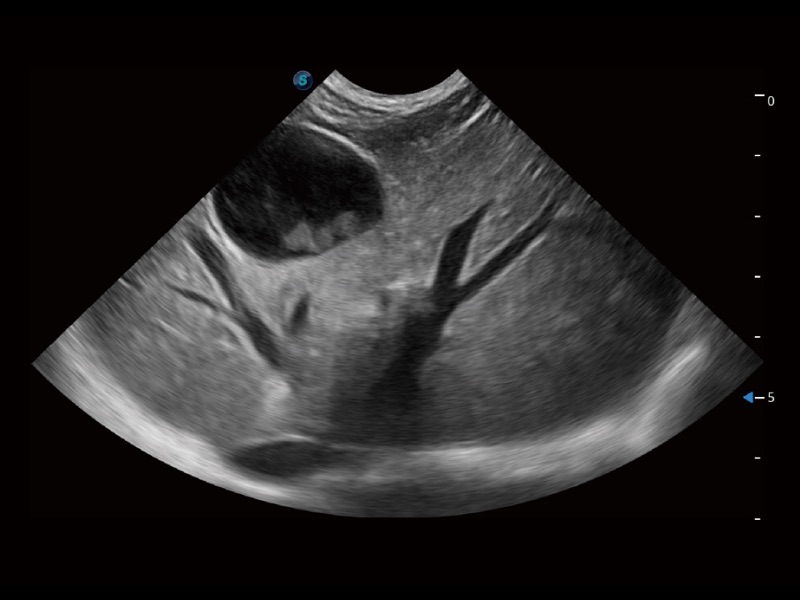

ProPet 70 進(jìn)一步提升了微米成像算法,更加注重對基礎(chǔ)原始圖像的還原和保留,在有效減少斑點(diǎn)噪聲、增強(qiáng)組織邊界顯示的同時(shí),避免過度優(yōu)化丟失真實(shí)的解剖信息。

為精細(xì)結(jié)構(gòu)及組織邊緣提供高清晰度的圖像和更大的成像視野。幫助減輕醫(yī)生的用眼疲勞,快速精準(zhǔn)獲得測量的數(shù)據(jù)。